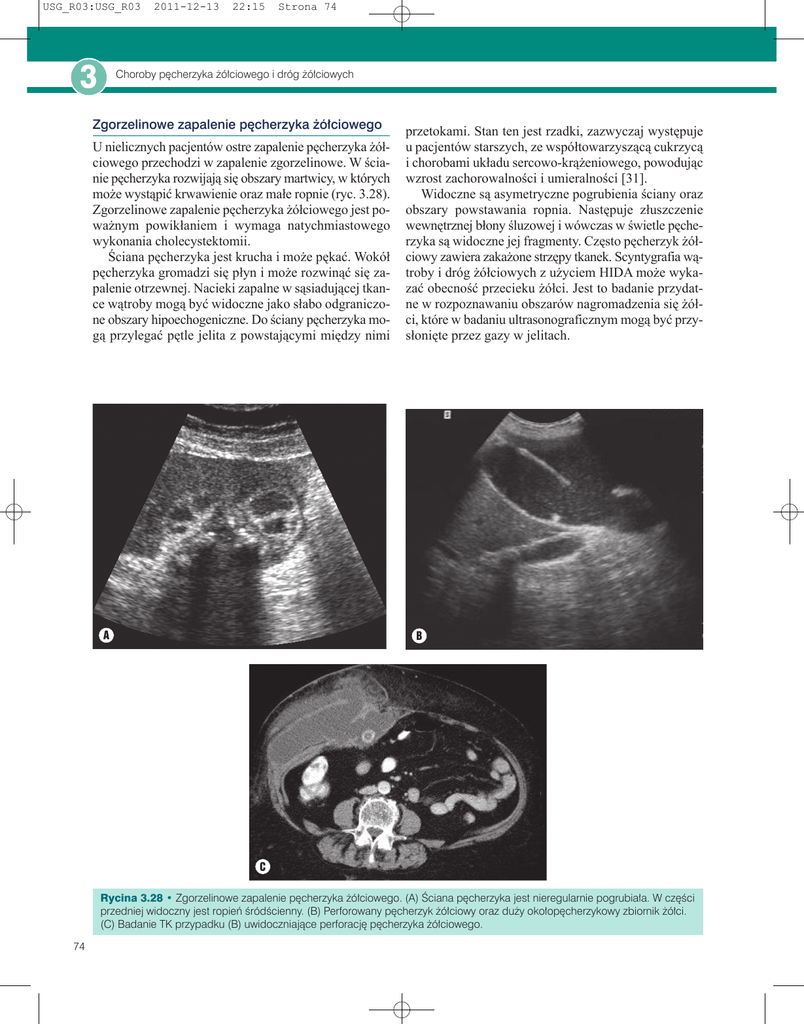

wewnętrznej błony śluzowej i wówczas w świetle pęcherzyka są widoczne jej fragmenty. Często pęcherzyk żółciowy zawiera zakażone strzępy tkanek. Scyntygrafia wątroby i dróg żółciowych z użyciem HIDA może wykazać obecność przecieku żółci. Jest to badanie przydatne w rozpoznawaniu obszarów nagromadzenia się żółci, które w badaniu ultrasonograficznym mogą być przysłonięte przez gazy w jelitach.

Rycina 3.28 • Zgorzelinowe zapalenie pęcherzyka żółciowego. (A) Ściana pęcherzyka jest nieregularnie pogrubiała. W części

przedniej widoczny jest ropień śródścienny. (B) Perforowany pęcherzyk żółciowy oraz duży okołopęcherzykowy zbiornik żółci.

(C) Badanie TK przypadku (B) uwidoczniające perforację pęcherzyka żółciowego.